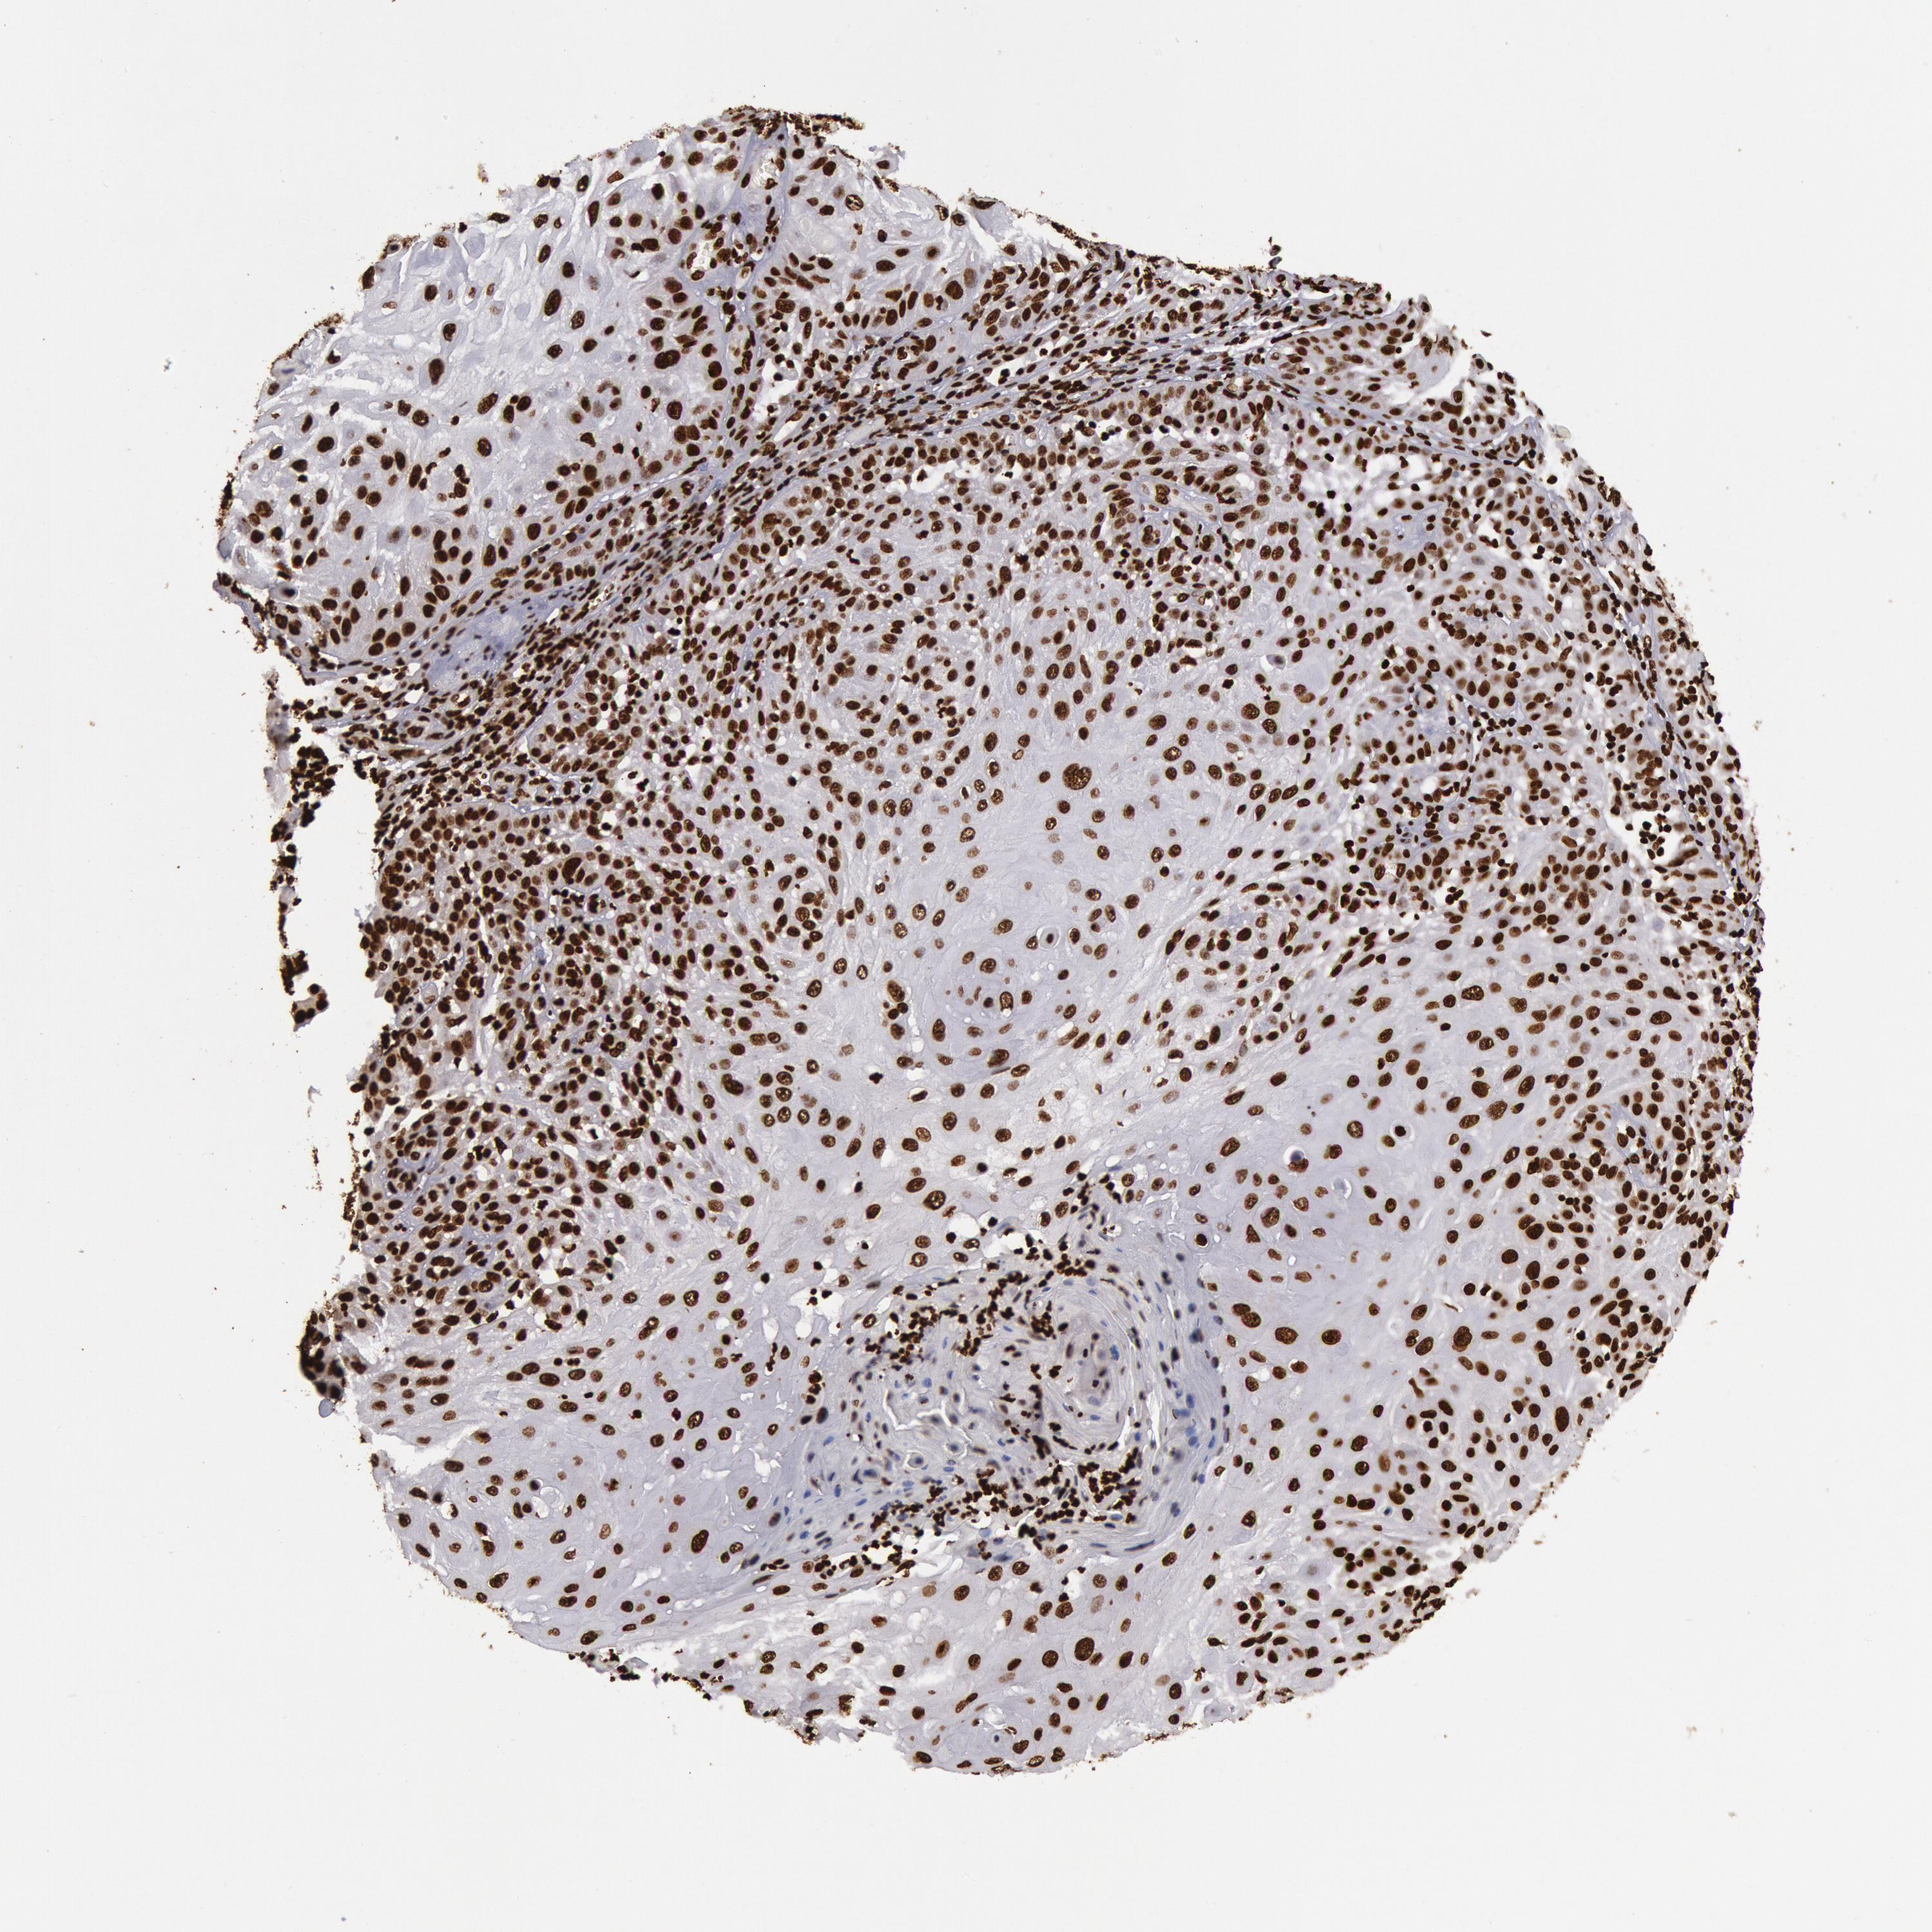

SKIN CANCER - Protein expressioni

A mouse-over function shows sample information and annotation data. Click on an image to view it in a full screen mode. Samples can be filtered based on level of antibody staining by selecting one or several of the following categories: high, medium, low and not detected. The assay and annotation is described here.

Each image is clickable and will lead to virtual microscopy that enables deeper exploration of all samples and also displays staining intensity scores, fraction scores and subcellular localization as well as patient and tissue information for each sample.

Antibody CAB003812

Squamous cell carcinoma, metastatic, NOS

Squamous cell carcinoma, NOS